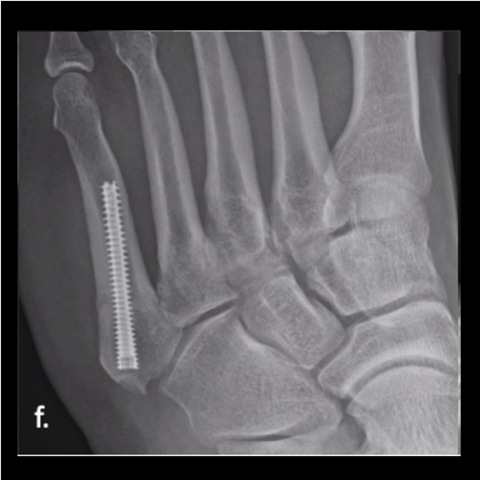

Figure 3f

Figure 3f. Here is the 28-year-old’s foot at 3 months.